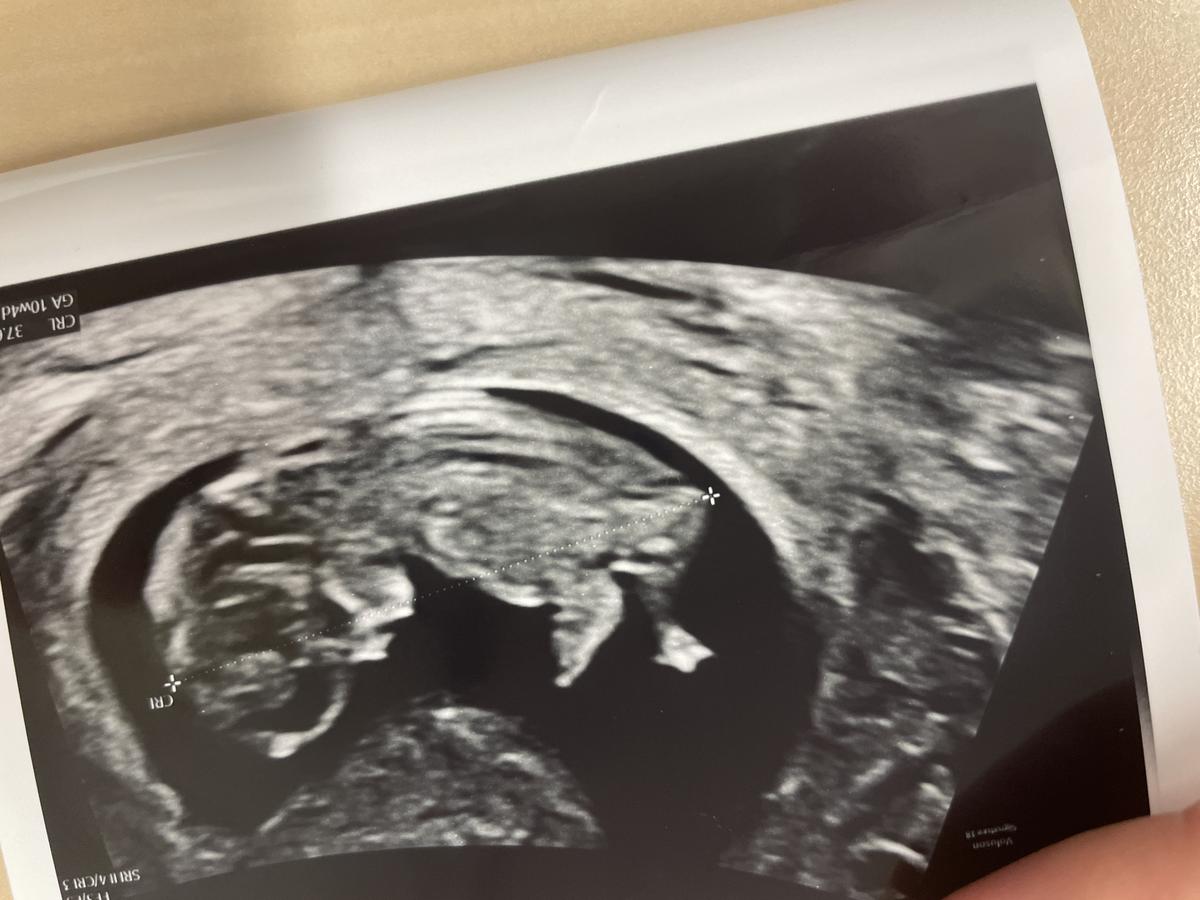

Echo uitdraai